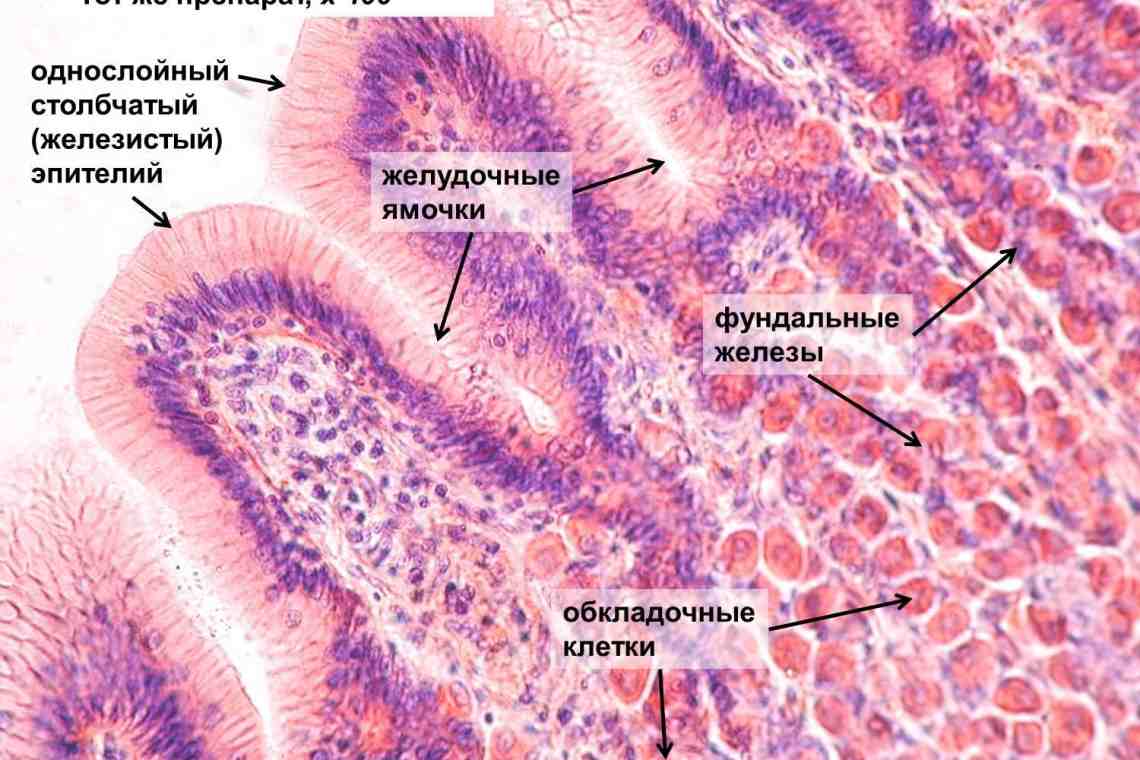

Исследование: микропрепарат молочной железы в медицине

Раздел: Снимки-откровения